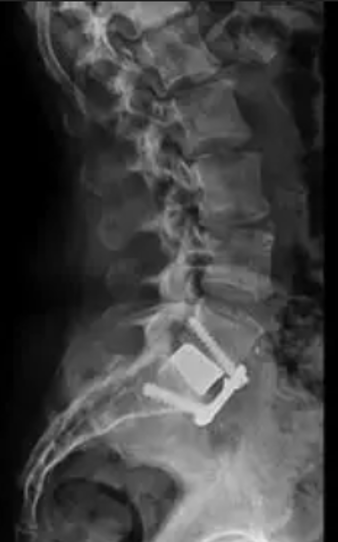

After Surgery Results

The surgeon removes the damaged disc or diseased bone, places a cage or bone graft between the vertebrae, and secures it with screws and rods. Over months, the bones heal together naturally. The surgical approach (front, back, or side) depends on the patient's specific condition and body type.